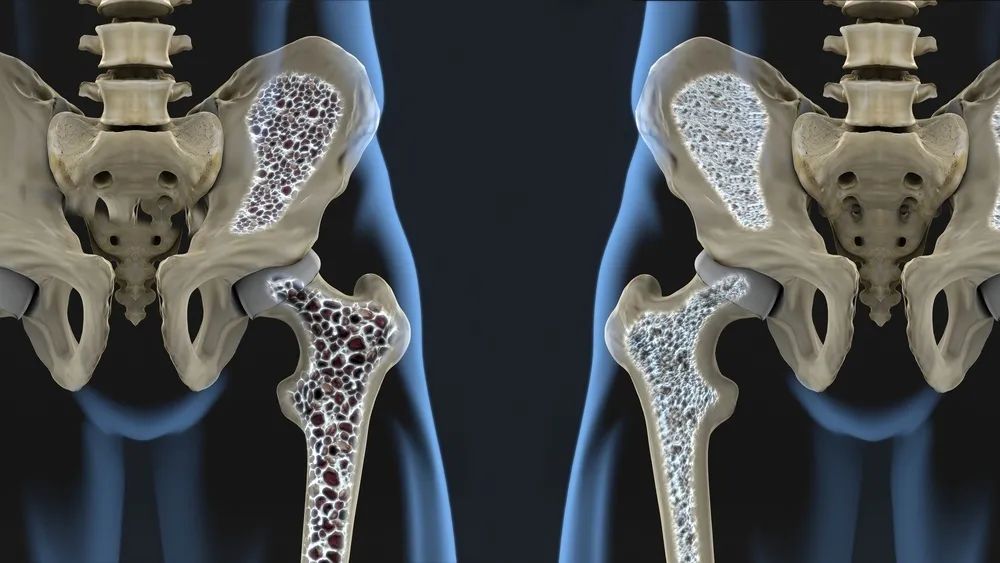

再来熟悉一下骨质疏松症的诊断:

骨质疏松定诊断标准:

T 值 ≤ -2.5:骨质疏松;

T 值 ≤ -2.5,且存在骨折:严重骨质疏松;